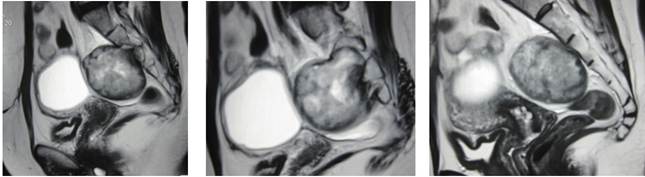

La paciente fue atendida y hospitalizada en el Hospital Nacional Edgardo Rebagliati Martins - EsSalud, Lima, Perú, debido al incremento paulatino de la intensidad de los síntomas, y se realizaron los estudios complementarios. El tacto rectal y la colonoscopía no encontraron hallazgos significativos. La resonancia magnética informó “una lesión sólida ovoidea en región presacra de 65 x 50 mm, que remodela el sacro por contacto directo, no es de origen óseo y se localiza a nivel de la tercera vértebra sacra. Además, describía la presencia de una lesión quística anexial izquierda de 55 x 45 mm” (Figura 2). La ecografía transvaginal evidenció una masa sólida heterogénea retrorrectal o presacra, que medía 65 x 55 x 48 mm.

Se decidió realizar una exploración quirúrgica con un abordaje anterior (abdominal), donde se identificó un tumor presacro de 60 x 50 x 40 mm adherido a la fascia presacra y el sacro a nivel de S3, encapsulado, poco móvil, de consistencia dura y coloración blanquecina, y una tumoración quística, adherida a trompa y ovario izquierdo, de 60 x 50 x 40 mm, móvil y de consistencia renitente. Se resecó la tumoración retrorrectal (Figura 3) y se practicó salpingooforectomía izquierda.

Las técnicas de imagen más utilizadas son la tomografía computarizada y la resonancia magnética, que confirman el diagnóstico de un tumor retrorrectal, sugieren el diagnóstico de Schwannoma, y sirven para planificar la técnica quirúrgica. La tomografía computarizada de la pelvis puede identificar tumores pequeños, distinguir una lesión quística de una lesión sólida y revelar el compromiso sacro o invasión de estructuras adyacentes, como en esta paciente.

La resonancia magnética de pelvis es particularmente útil para delinear planos de tejidos blandos, delimitar claramente la presencia de una cápsula y evaluar la presencia o ausencia de invasión ósea y afectación nerviosa, por lo que se constituye en el procedimiento diagnóstico de elección para este tipo de tumores 7,10. La diferenciación entre Schwannomas benignos y malignos, así como entre Schwannomas y otros tumores de tejidos blandos, como fibrosarcomas y liposarcomas, constituyen un desafío debido a la falta de características distintivas 4.